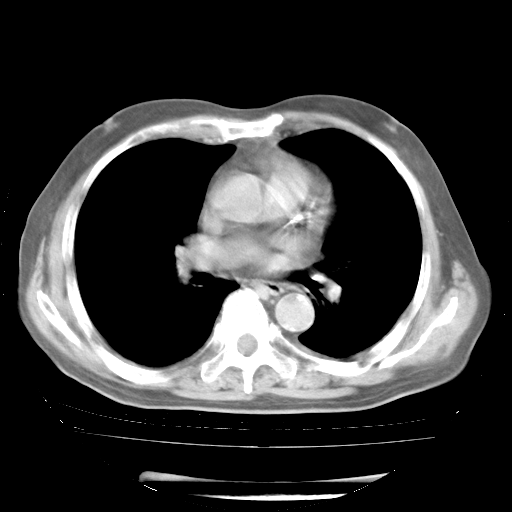

4月28日肺部CT

1、108#的是4月14日的胸部CT(发此贴时还没看着28日的CT)。14日的胸部CT其实已经出现改变(如108#所述),个人认为28日的胸部CT除纵膈窗疑似有双侧胸膜增厚或少量胸积液(可行胸部B超明确)外,与4月14日对照病变有所加重;2、已经给予“异烟肼、利福平、乙胺丁醇”抗痨治疗?如果是,甲强龙80mg可缓慢减量;如果环磷酰胺已停用,暂不使用;3、中性粒细胞92%,明显升高,目前体温情况?注意合并细菌感染可能,使用左氧氟沙星情况下,是否联用B-内酰胺类抗菌药物?另外是查免疫全套非风湿全套。

今请临免主任会诊后认为:4月14日胸部CT已有双下肺间质性改变。患者病情复发多系激素减量过快不正规所致。目前甲强龙80mg/日,一周后酌情开始减量,不易过快。环磷酰胺若已停用,暂不使用。他同意目前抗菌药物使用,但应考虑是否加用B-内酰胺类抗菌药物(中性细胞明显增高);2、结核复发目前依据不足;3、若免疫全套各项指标正常,考虑多系特发性肺间质炎可能大。4、加强支持,并注意保护胃黏膜。